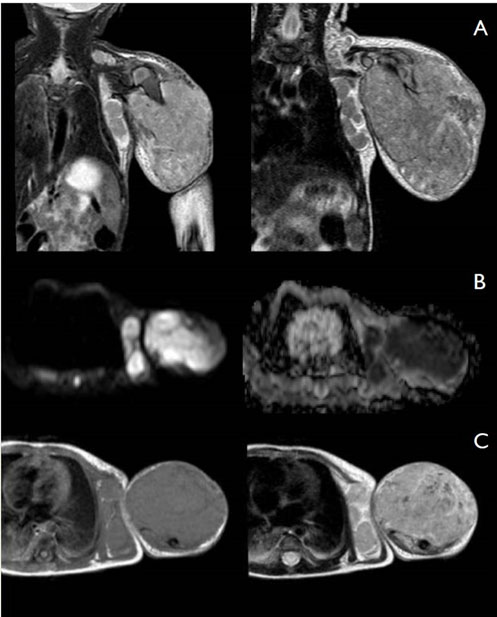

Magnetic resonance imaging (MRI) of left upper arm and shoulder area showed a large, multilobular soft tissue mass extending from left shoulder till the elbow with intrathoracic and supraclavicular invasion. The mass was hyperintense with adjacent muscle in T2-weighted sequences and nearly isointense in T1W (Figure 2). There was restricted diffusion in diffusion weighted imaging, suggestive of hypercellularity. Post-contrast T1W MRI showed mild enhancement of the mass. There were multiple enlarged left axillary, supraclavicular and inferior jugular lymph nodes. Bone invasion was noted. The differential diagnosis suggested by MRI was of a highly aggressive, hypercellular soft tissue tumor such as rhabdomyosarcoma, MRT, infantile fibrosarcoma, peripheral primitive neuroectodermal tumor, and epithelioid sarcoma [10].

Figure 2: MRI features of rhabdoid tumor of left upper arm with intrathoracic and supraclavicular extension: (A) Coronal short inversion time inversion-recovery (STIR) (left, as seen in the image) and T2W (right) demonstrate a large, solid mass with high signal intensity compared with adjacent muscle. (B) Transaxial diffusion-weighted sequence show high signal intensity on diffusion weighted imaging (DWI) (left) and low signal intensity on corresponding apparent diffusion coefficient (ADC) map (right) reflecting the aggressive biological behavior of the tumor. (C) Axial T1 pre-contrast image (left) demonstrates isointensity of the mass and mild enhancement on post-contrast T1 sequence (right).